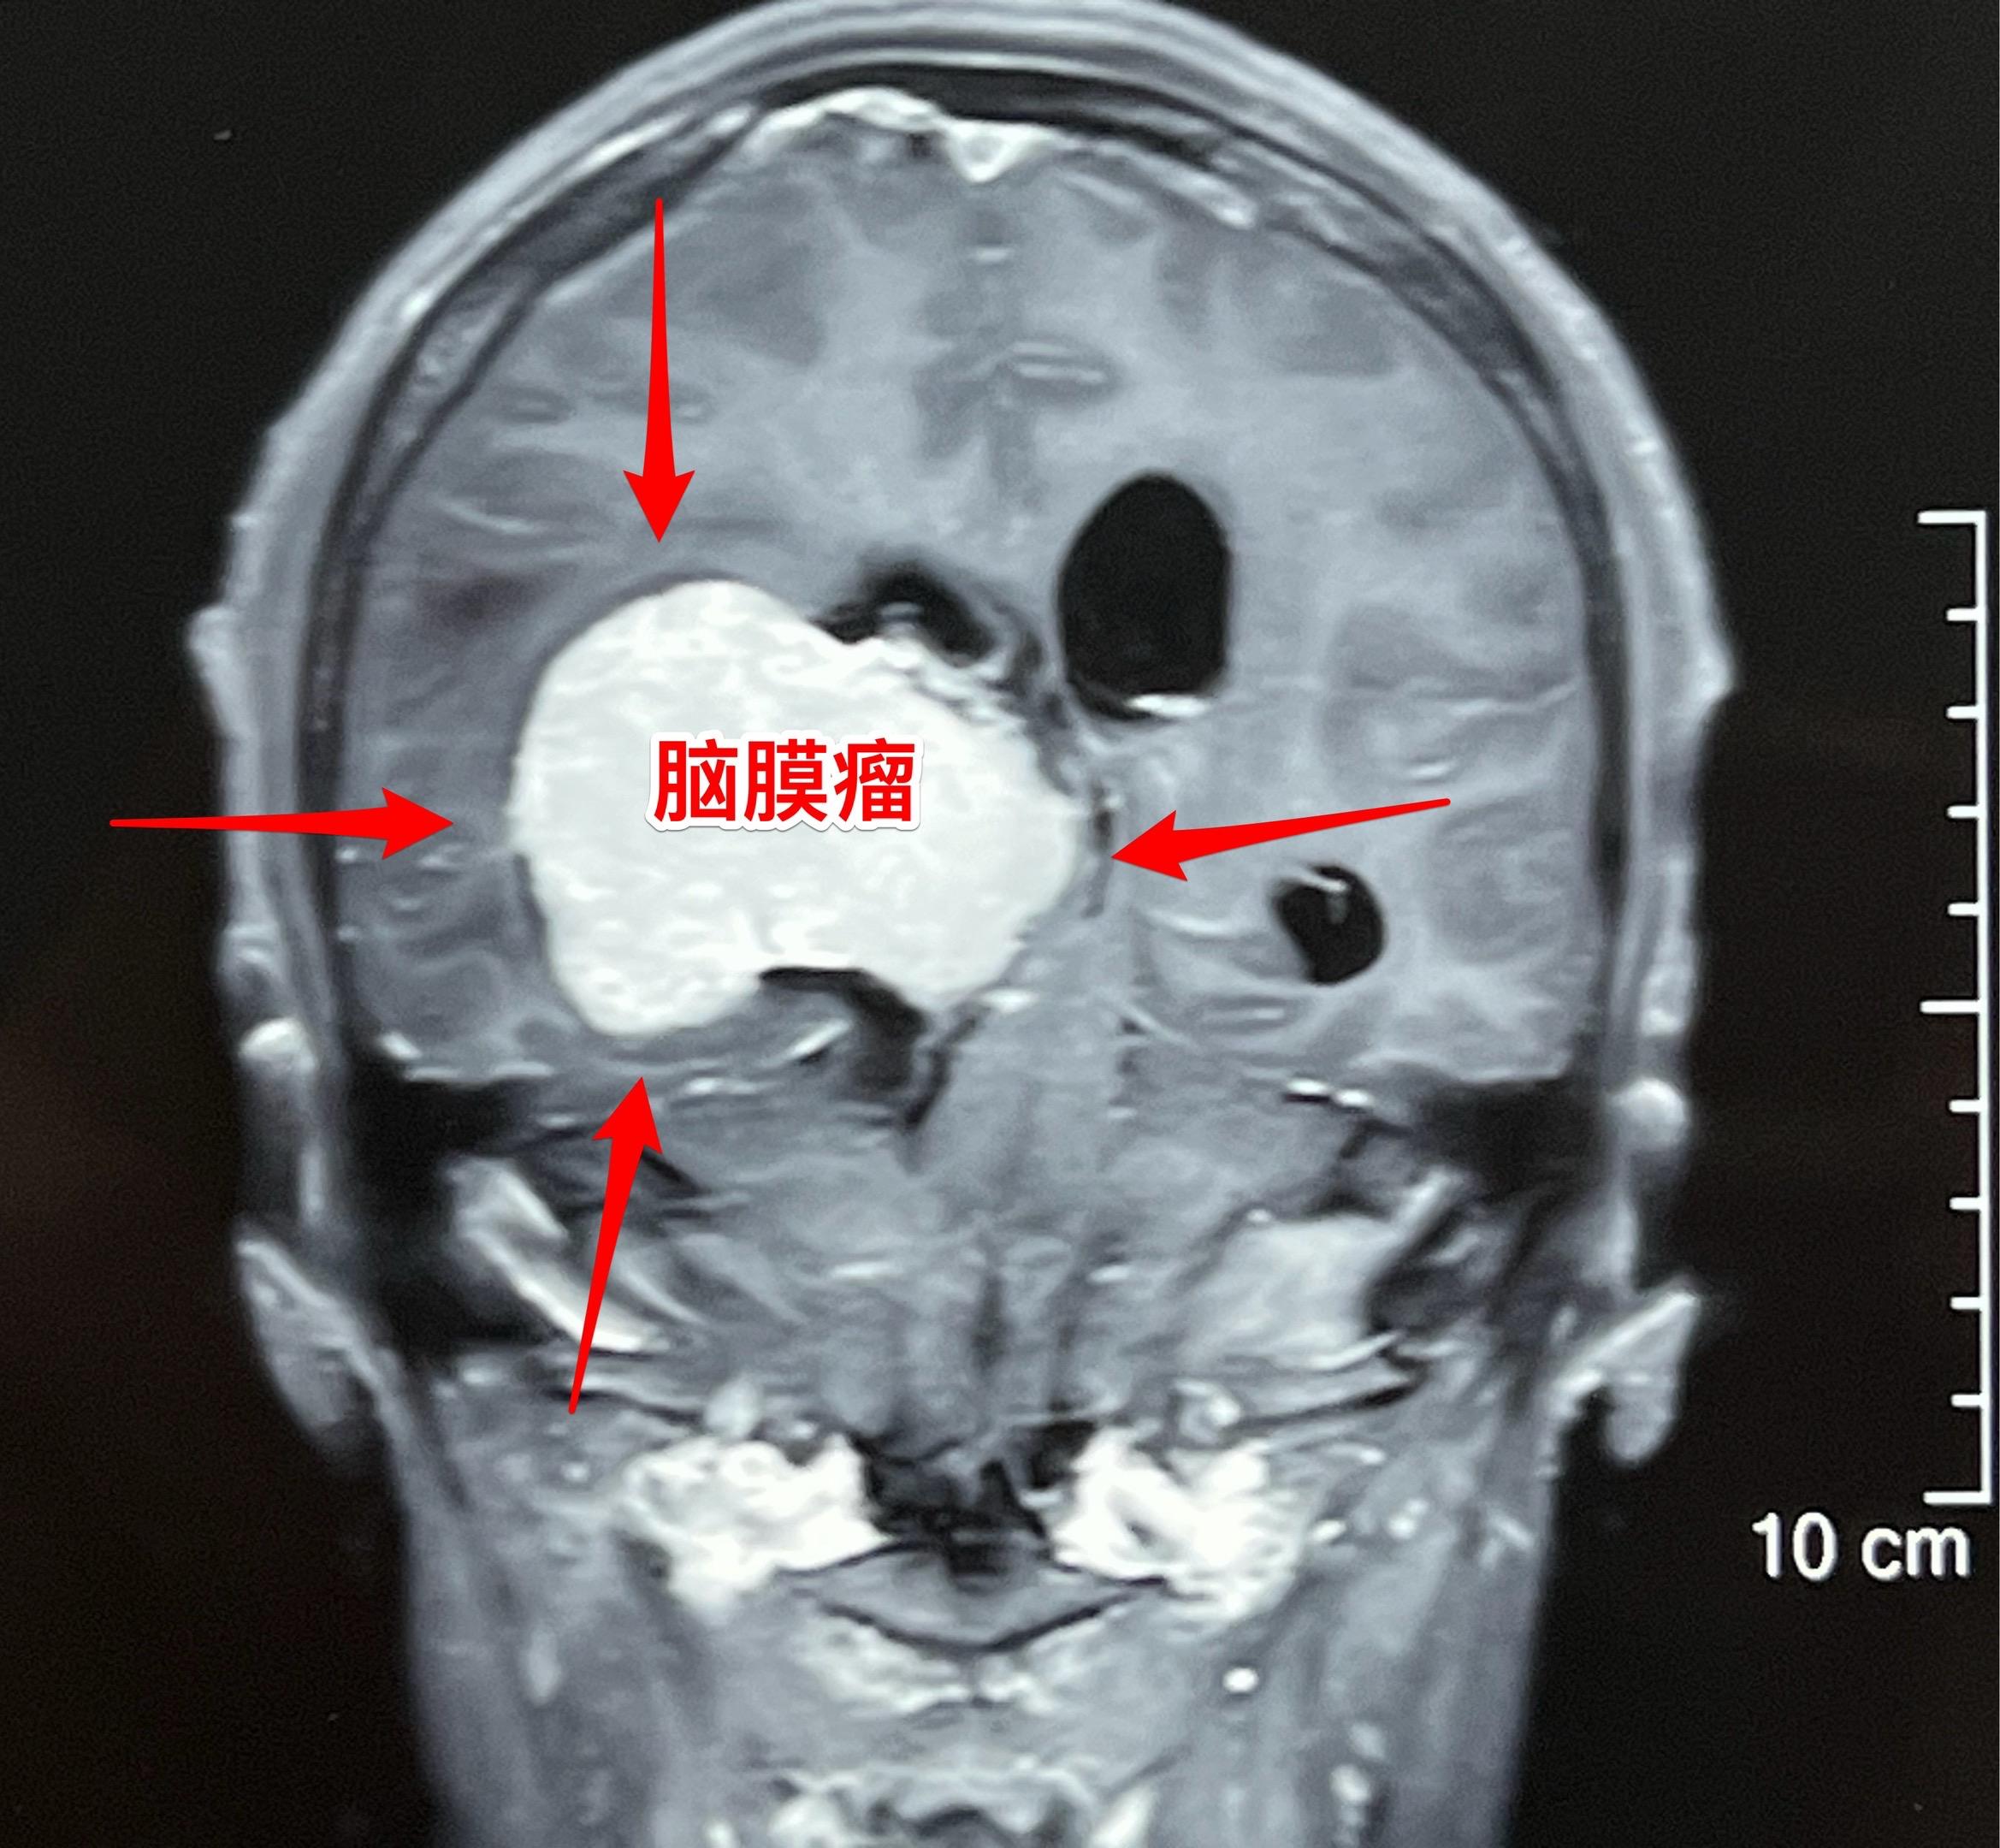

脑室内脑膜瘤也是良性肿瘤。49岁朝鲜族女性,在韩国工作,因头痛、呕吐发现这个肿瘤,随即回国治病。 这个肿瘤位于右侧脑室的三角区,脑室内的脑膜瘤最好发于这个位置。如果作手术彻底切除这个肿瘤,可以获得治愈。